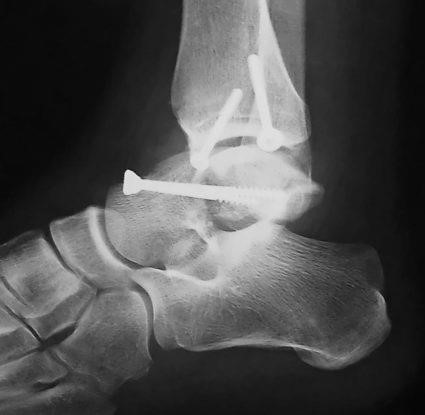

Определить окончательный диагноз и необходимое лечение поможет только рентгенологическое исследование, которое проводят в двух проекциях. Также врач может назначить проведение томографии – компьютерной или магнитно — резонансной. Благодаря таким методам диагностики, можно обнаружить наличие даже малейших повреждений, которые могут быть не замечены при рентгенологическом исследовании.

В том случае, если в процессе нескольких попыток не удалось сопоставить отломки кости, назначается открытая репозиция и фиксация с помощью спиц Киршнера. Процесс контролируют с помощью рентгена. При разрушении суставной поверхности блока таранной кости также проводят артродез сустава. Наиболее тяжелые случаи требуют удаления кости.

Устранить переломовывих кости можно только оперативно. Но даже такой метод лечения будет крайне затруднителен. Как только вывих вправлен и проведена точная репозиция отломков, зону перелома фиксируют специальными спицами. Репозиция может быть затруднена, если угол поворота тела кости – более 90°. Спустя один месяц проводят удаление спиц, замену наружного гипса, который теперь накладывают вплоть до колена. Гипс при этом содержит вмонтированный металлический супинатор.